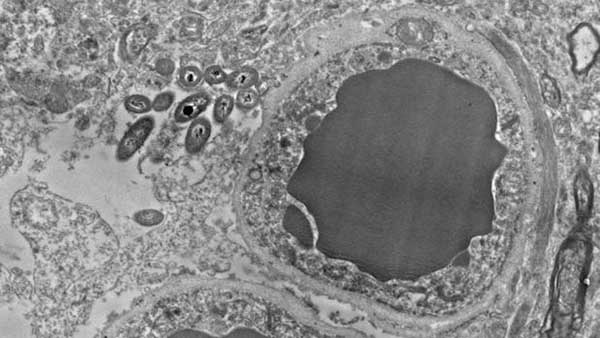

Fotografía de un astrocito, una célula de soporte de las neuronas. La mancha gris del centro es un capilar, a la izquierda, varias bacterias - ROSALINDA ROBERTS, COURTNEY WALKER, AND CHARLENE FARMER

Gracias a fotografías hechas con microscopio electrónico, los investigadores han observado que hay grupos de bacterias muy abundantes en el intestino viviendo dentro de los astrocitos, unas células de apoyo de las neuronas, y también dentro de algunas neuronas. Esto parece ocurrir tanto en cerebros sanos como en cerebros que padecen esquizofrenia. Por el momento, se desconoce si estos microbios tienen algún papel beneficioso, perjudicial o inocuo.